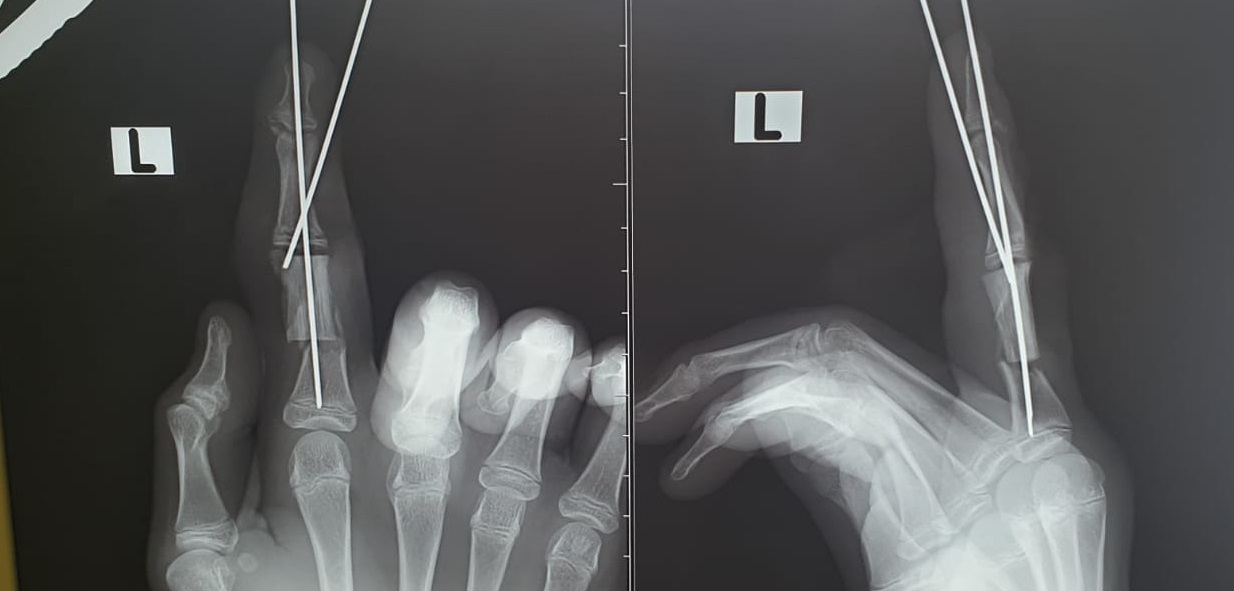

- Мы диагностировали неполную травматическую ампутацию указательного пальца и скальпированные раны среднего пальца. Половина основной фаланги указательного пальца отсутствовала, она была размозжена. Палец держался на сосудисто-нервных пучках. Нам нечем было закрывать большой дефект кости, речь шла либо об укорочении пальца, либо о замещении поврежденного участка собственным фрагментом кости пациента - так называемой аутотрансплантации , - сообщил детский хирург Михаил Азаров. |

Операция продлилась более трёх часов и завершилась успешно. Мальчик продолжает лечение в клиники вуза.

- Важно понимать, что, так как пациент травмировал суставную поверхность, ему потребуется длительная реабилитация, и могут быть ограничения в подвижности пальца, - сообщил Михаил Азаров. |